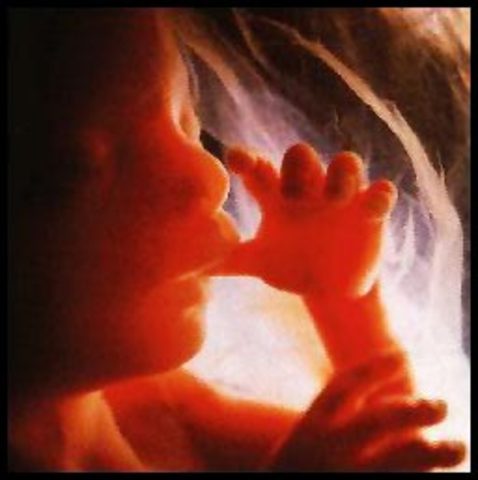

• 7 weeks

7 weeks

photo of thumb sucking